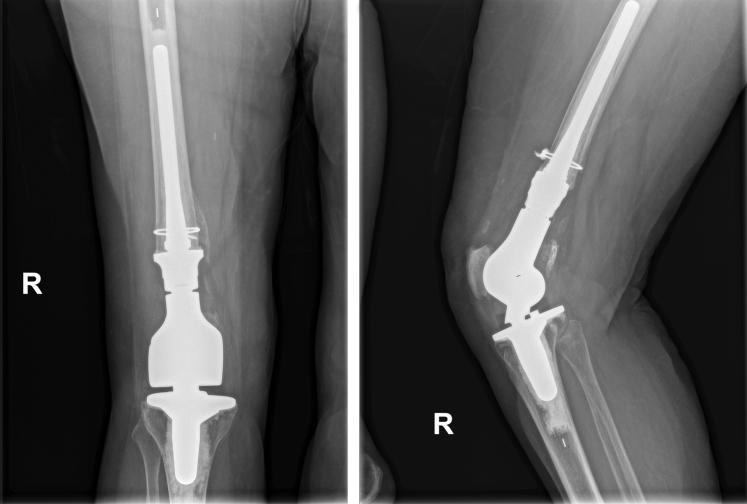

Single-stage bilateral distal femur replacement for traumatic distal femur fractures.

Treatment of periprosthetic distal femur fractures and comminuted intraarticular distal femur fractures with previous arthritis remains a difficult challenge for orthopedic surgeons. Previous case series have shown that distal femur replacement (DFR) can effectively compensate for bone loss, relieve knee pain, and allow for early ambulation in both of these fracture patterns. Owing to the typical low-energy mechanism of these injuries, a bilateral injury treated with DFR is rarely encountered. We present a patient with traumatic open left Rorabeck III/Su III periprosthetic distal femur fracture and closed right intraarticular distal femur fracture (AO fcation 33-C2) with end-stage arthrosis treated with single-stage bilateral DFR. We suggest that in patients with similar injuries, single-stage bilateral DFR can provide the benefits of early mobilization and accelerated recovery.